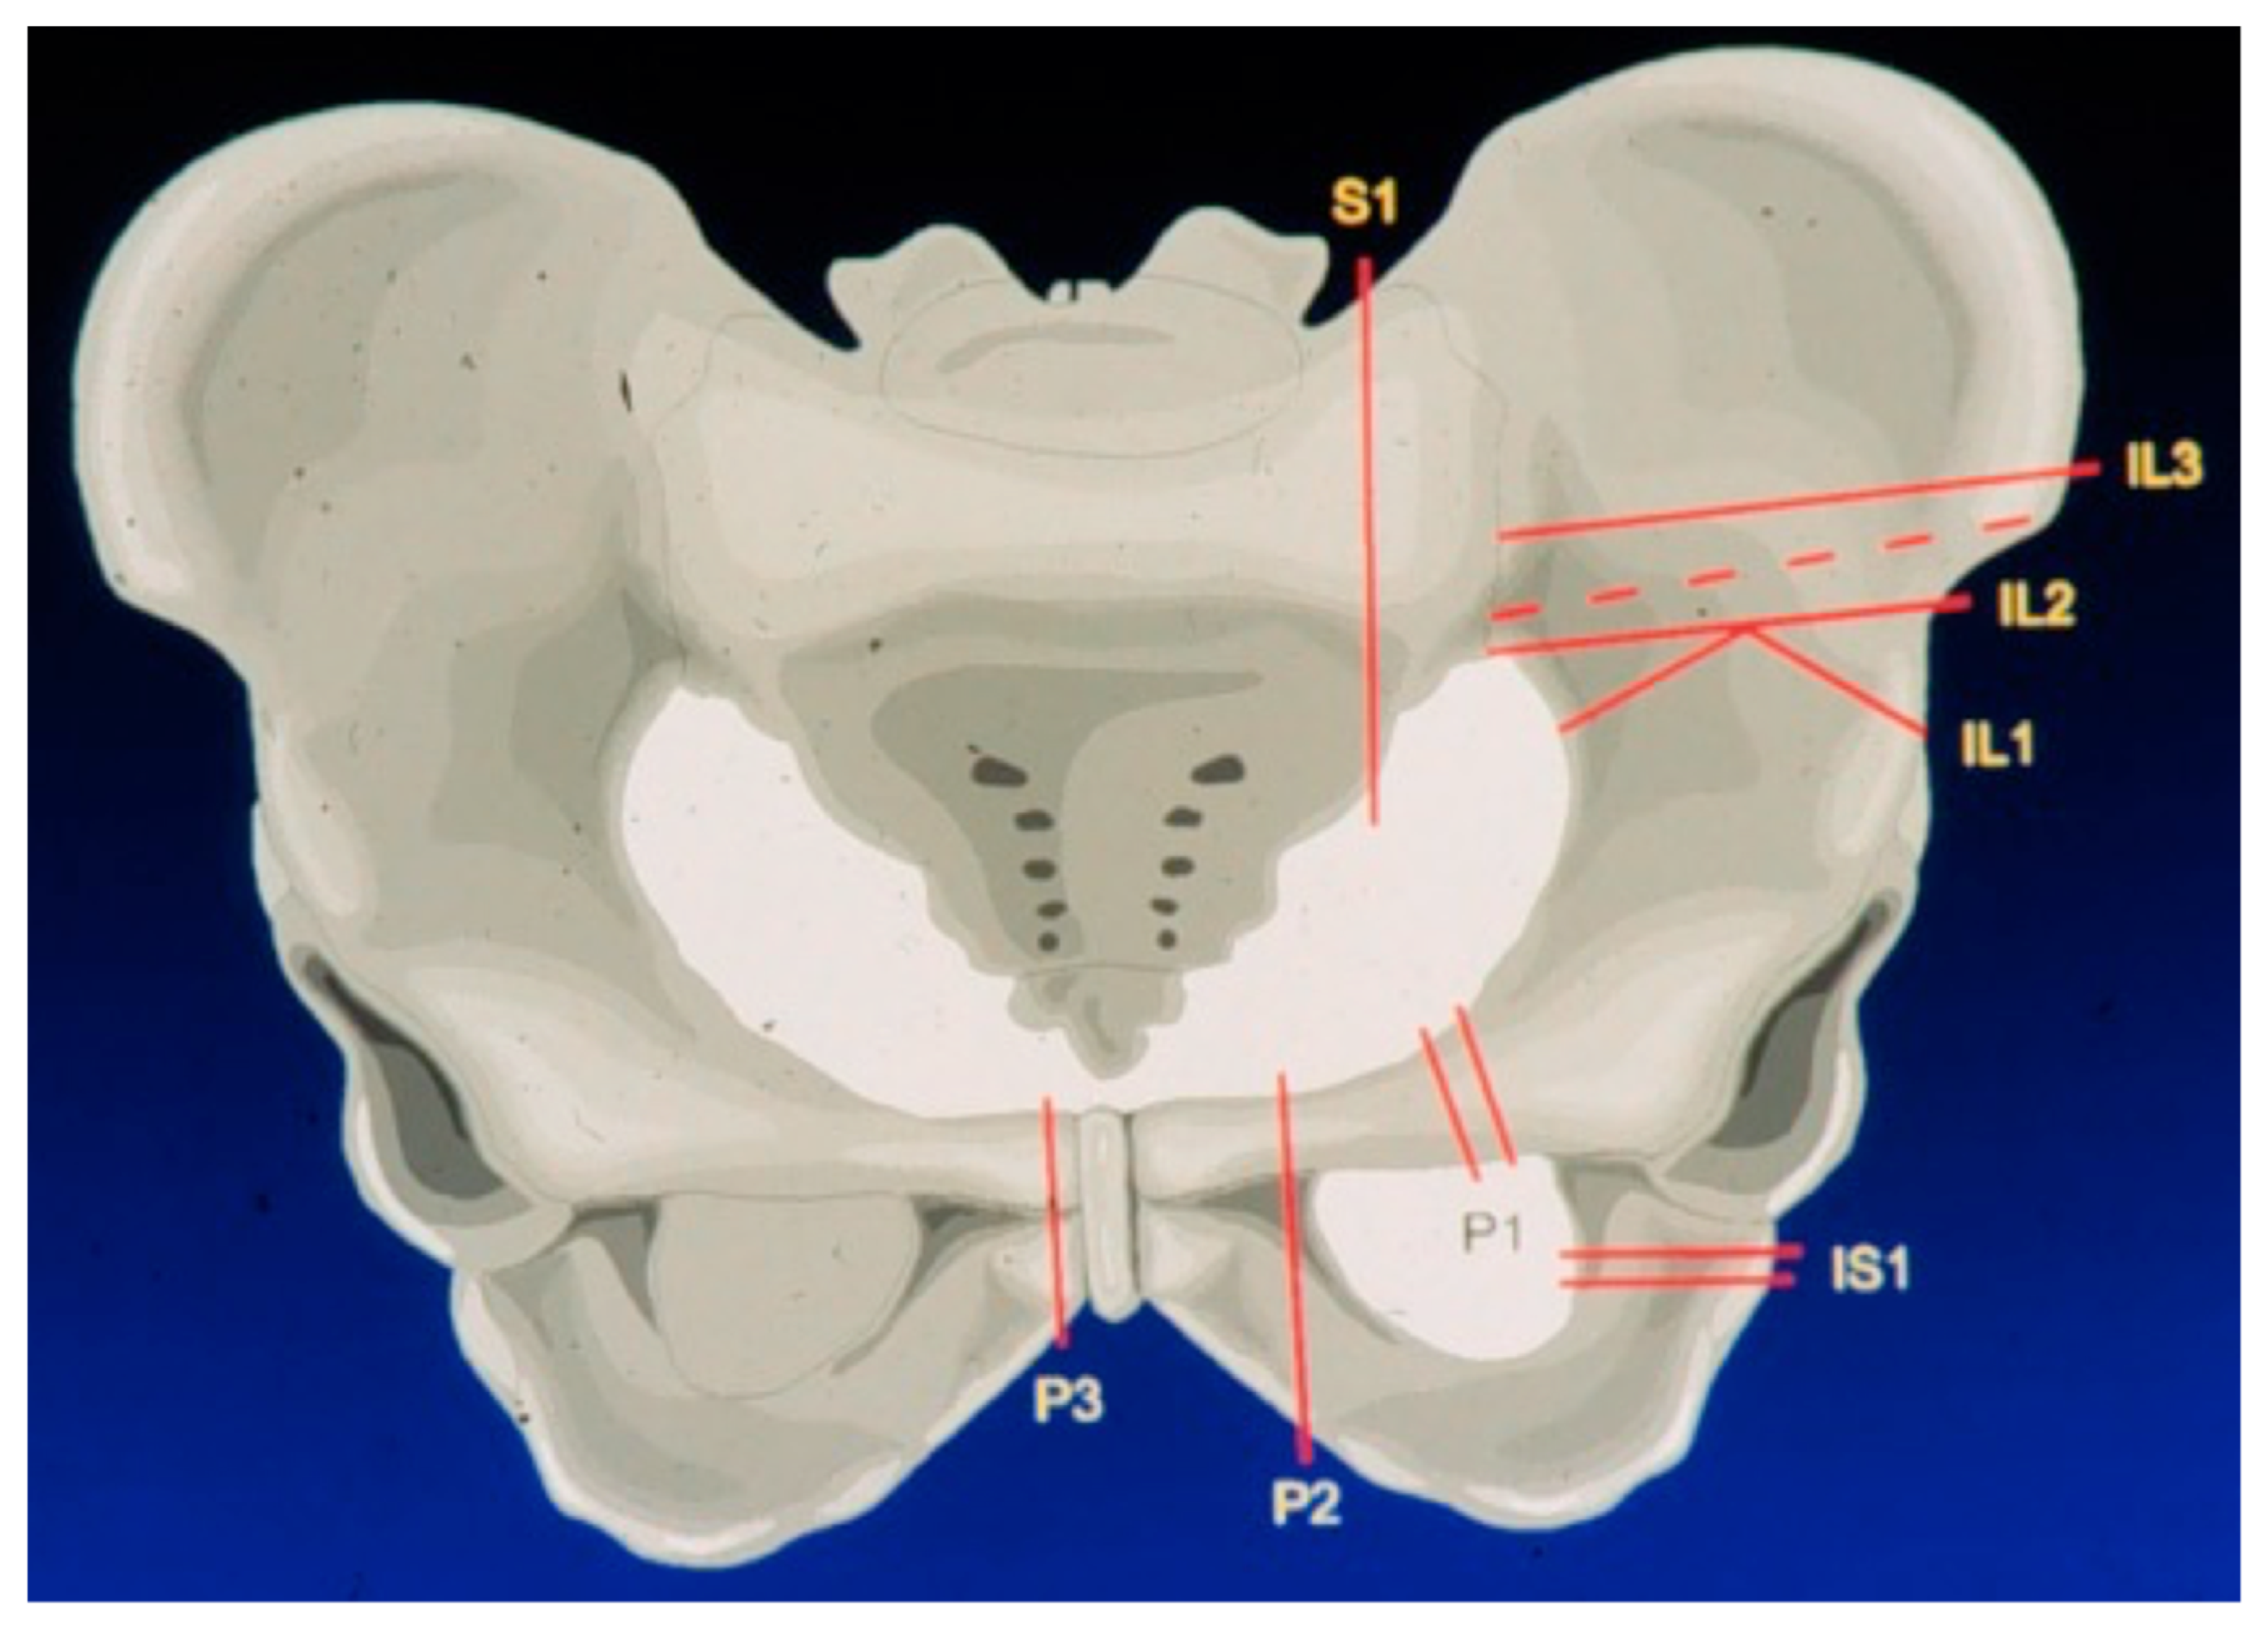

| Type of internal hemipelvectomy (Enneking/Dunham) | ||

| I–IV | 8 | 0.6 * |

| I, II, III | 3 | 0.6 * |

| I, II | 3 | 0.5 * |

| II, III | 2 | 0.8 * |

| I, II, IV | 2 | 0.7 * |

| N/A | 2 | 0.5 * |